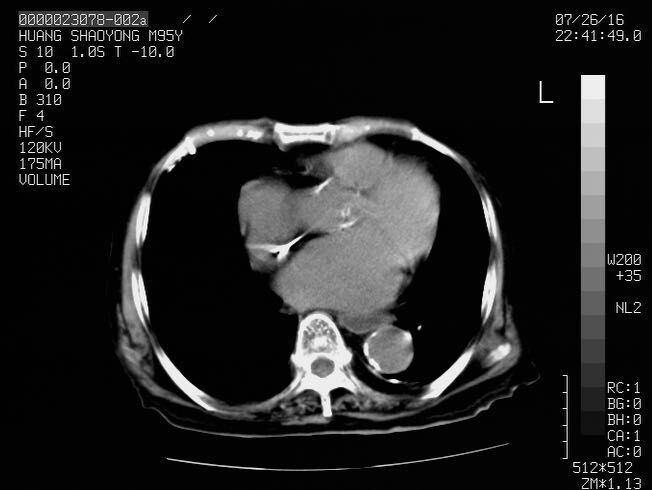

本帖最后由 cefcmj 于 2016-7-29 13:04 编辑 男,95岁,不全性肠梗阻查因

回亡部肠腔狭窄似有占位

右侧回盲部确实应该考虑有占位的可能,在下漏掉了。但左侧结肠似乎也是扩张的,应该再往下扫描,看看有梗阻的原因没~~~~

没扫全啊,考虑低位小肠梗阻可能性大;完全还是不完全要结合临床症状;胃肠道功能紊乱也可以这样的影像表现 ...